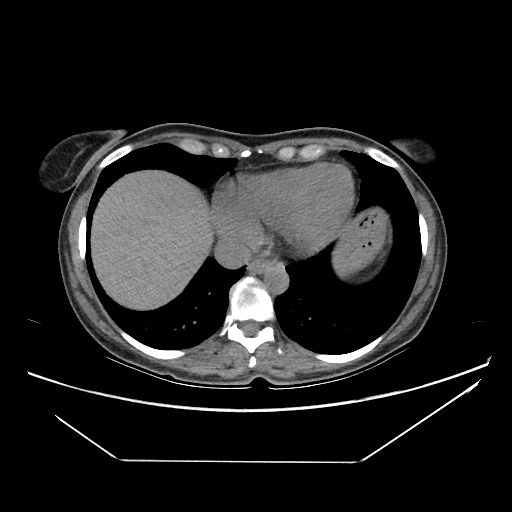

Original VENOUS CT scan

Full window (WL 1023.5, WW 4095 β†’ Low βˆ’1024, High +3071)

Actual HU range: [-160.0, 240.0]

Lung window (WL -600, WW 1500 β†’ Low βˆ’1350, High +150)